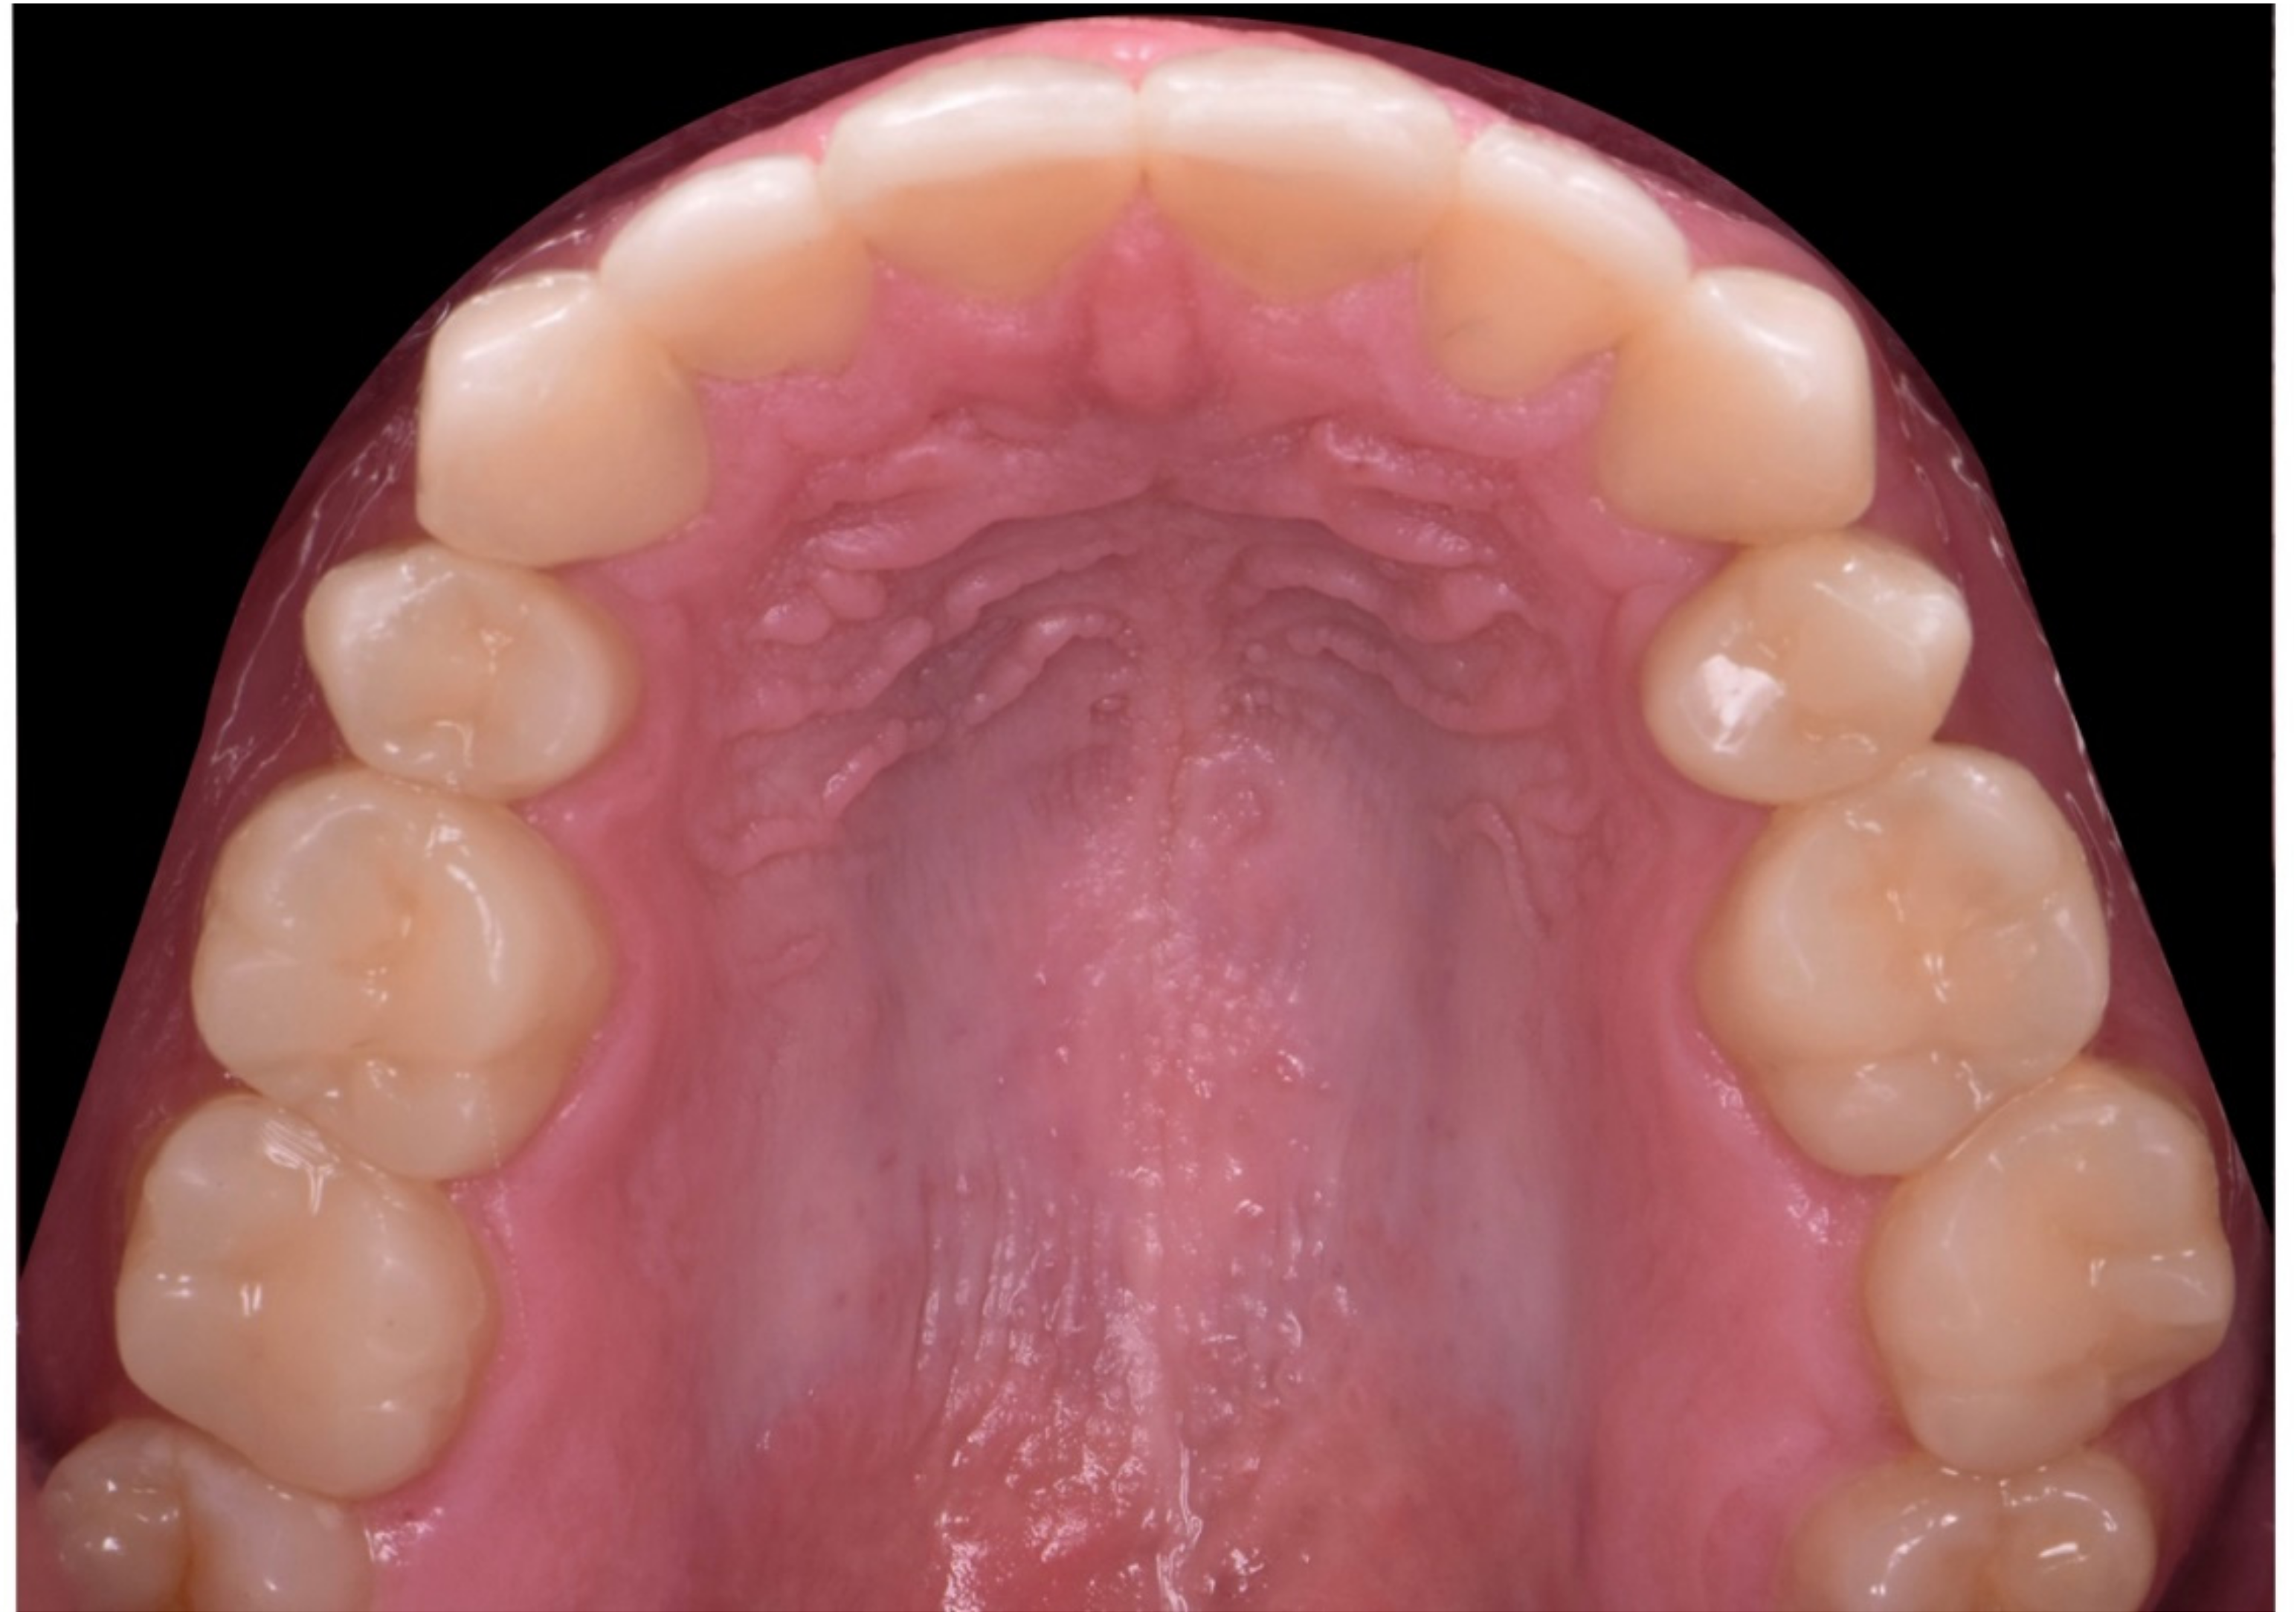

2. Clinical Report

2.1. Planning Phase

2.2. Restorative Phase